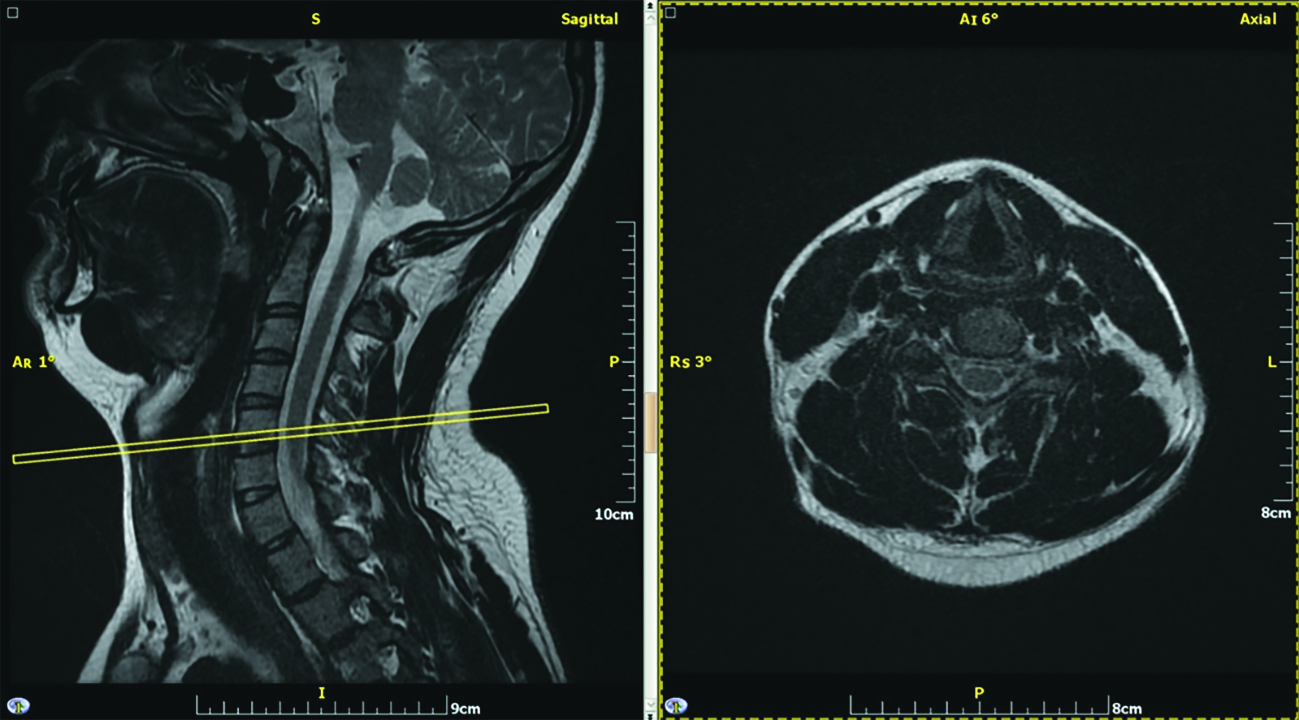

Участники наблюдения были разделены на группы с учетом выраженности дегенеративно-дистрофических изменений шейного отдела позвоночника. В первой группе не было отмечено значимо выраженных структурных изменений межпозвоночных дисков и тел позвонков. Вторая группа включала случаи с преимущественными изменениями межпозвоночных дисков и слабовыраженными изменениями тел позвонков в виде заострения углов. В третьей группе были представлены случаи наблюдения с выраженными проявлениями остеохондроза и спондилеза. Проводилось измерение длины и ширины тел позвонков в аксиальной (поперечной) плоскости. Оценка выполнялась вблизи замыкательных пластин тел позвонков. Пример визуализации представлен на рисунке 1.

Рисунок 1. Участник №20, женщина, 26 лет. МРТ в режиме Т2, выполненные в сагиттальной плоскости и поперечно на уровне С5 позвонка, диагностическое оборудование – 1,5 Тл Brivo MR355 (General Electric, USA).

Figure 1. Participant No. 20, female, 26 years old. MRI in T2 mode, performed in the sagittal plane and transversely at the C5 vertebra level, diagnostic equipment – 1.5 Tl Brivo MR355 (General Electric, USA).